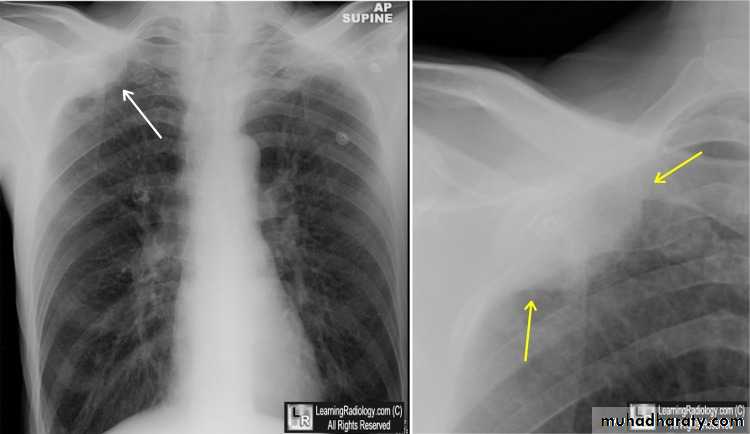

Diseases of the pleura• 1-Spontaneous pneumothorax

Is the accumulation of air inside the pleural cavity , occurring without any known etiology .More in males ,more on the right side .It can be bilateral

• Causes 1- Ruptured pulmonary bleb.2-Ruptured of a cystic defect in the pleura.3-Teared visceral pleura 4-No cause can be demonstrated in (15-20%).Complications:-1-pleural effusion2-empyema 3-tension pneumothorax which leads to mediastinal shift &circulatory collapse.4-Respiratory failure in elderly patient with COAD .

• Treatment :-

• 1-Bed rest ,O2 administration &observation in limited pneumothorax.

• 2-Aspiration

• 3-Chest tube (thoracostomy tube or ICD intercostal drain in a safety triangle which is bounded by pectoralis muscle anteriorly &lattismus muscle posteriorly and the superior border of the nipple.in the fifth intercostal space just anterior to the mid axillary line to avoid the long thoracic nerve .